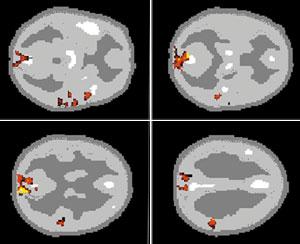

Исследование мозговой организации творческого мышления.

При сравнении физиологических процессов мозга, зарегистрированных в процессе составления испытуемыми рассказа из слов разных семантических полей (задание с выраженными элементами творчества) и в процессе восстановления связного текста с изменением словоформ (такие элементы отсутствуют), выявлены достоверные локализованные различия.

В левой части представлены различия характеристик межзональных связей ЭЭГ по оценкам межзональных кросскорреляционных функций.

Средние данные по группе испытуемых. Связи отображены линиями, соединяющими места размещения соответствующих электродов. Красный цвет соответствует усилению связей, голубой - уменьшению. Толщина линий отражает уровень статистической достоверности различий связей.

Достоверные различия обнаруживаются главным образом в межполушарных связях. Наиболее выражен эффект творческих элементов задания в возрастании связей левой передневисочной зоны, охватывая и другие зоны передней доли мозга. При этом связи передневисочной и переднелобной зон правого полушария усиливаются с передними зонами коры и ослабляются с задними. Ослабляются также связи теменных и затылочных структур коры между собой.

В правой части показаны различия в возрастании локального мозгового кровотока при выполнении таких же заданий испытуемыми.

Средние данные по группе испытуемых. Сверху - левое полушарие, Внизу - правое.